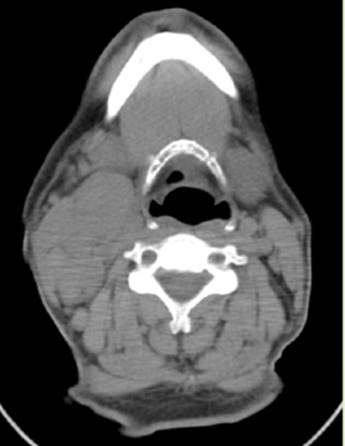

Al momento del diagnóstico el paciente se encuentra sin criterio de tratamiento, pero pasado un año desarrolla adenomegalias latero-cervicales derechas con LDH normal (Figura 1).

Figura 1. Corte axial de tomografía computada donde se observa adenomegalia a nivel cervical.